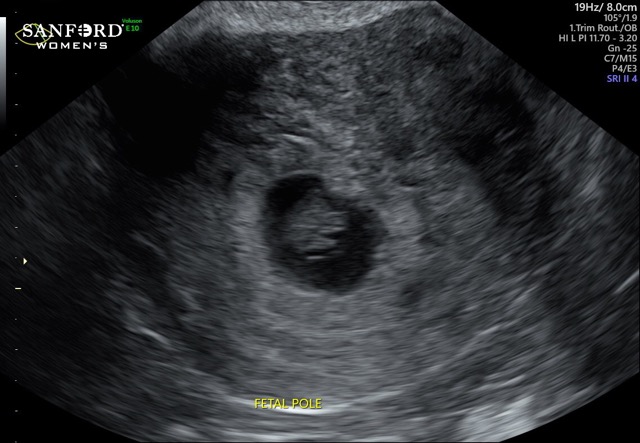

Hey all! Currently 9 weeks pregnant.. I can’t sleep because my mind won’t shut off! My mom was diagnosed with stage 4 cancer in August and we go in for PET scan results tomorrow morning... so stressful, gives me so much anxiety and I know it’s not good.... any suggestions on ways to cope with something like this? Life sure is hard sometimes.... and add these pregnancy hormones. Man. Life,can,be.Rough!

Ty! Pic for attention.